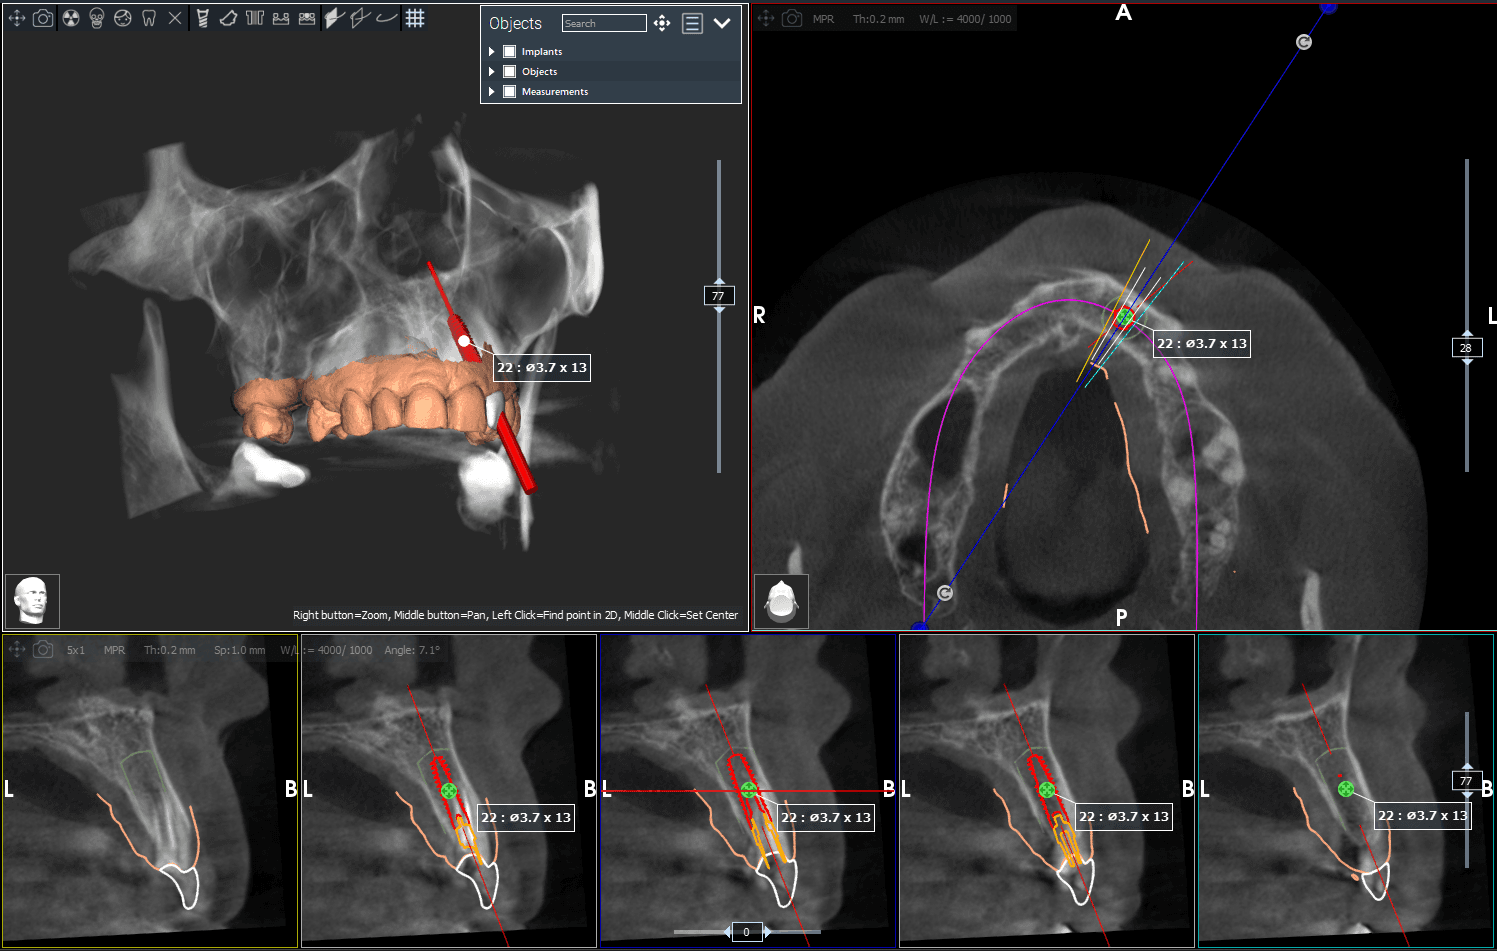

3D CBCT-scan: Voor complexe diagnostiek en implantaatplanning maken we een 3D-scan terwijl je gewoon staat. In slechts 13 seconden hebben we een haarscherp beeld, zonder dat je in een nauwe tunnel hoeft te liggen.